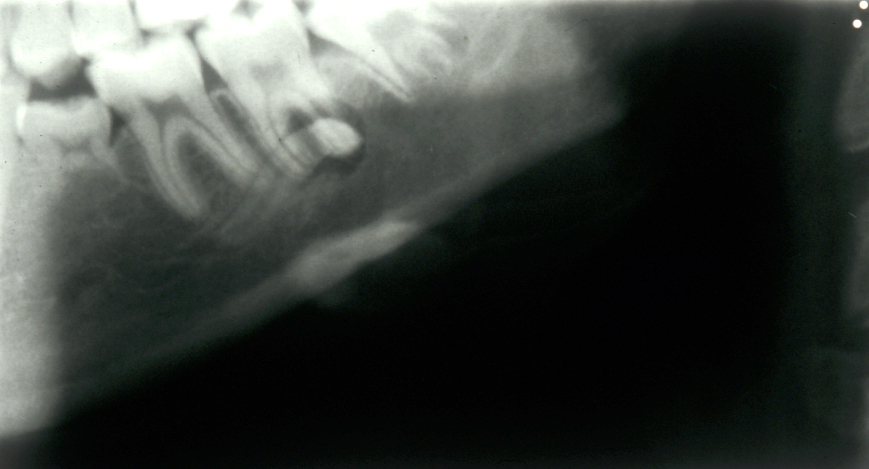

Assessment of the tooth is both clinical and radiographic. If somebody presents in pain, it is important to establish that this is coming from the third molar and not elsewhere. Pain is often vague, poorly localised and may be referred from another tooth, or as part of facial arthromyalgia (condition affecting the jaw joint). A dental panoramic radiograph is ideal as it helps to assess all the teeth at once. The health of the adjacent molars may influence the decision whether to remove the third molar or not. Large crowns or old restorations are all at risk of dislodgement during surgery. It is also worth considering whether alternative treatment options are available. For instance, pericoronitis due to an over-erupted upper third molar may be dealt with by extracting that tooth only, with or without operculectomy. In the presence of other teeth of poor prognosis, will it be better in the long term to save the third molar which may be used as a denture or bridge abutment in the future?

Having established that the wisdom tooth needs to be removed, other points in the assessment include:

- tooth position (vertical, mesioangular, distoangular, horizontal or across the arch).

- depth and degree of impaction;

- obstruction to eruption (what is the tooth impacted against?);

- root morphology (the curvature of the roots controls the path of withdrawal);

- relationship to the inferior dental nerve canal;

- associated pathology (for example, cysts);

- bone density;

- status of second molar tooth (in selected cases where this tooth has a poor prognosis it may be better to extract it and leave the third molar).

These points help to determine whether the tooth can be simply elevated or will need a surgical approach. A series of radiographs depicted in Figure 4 to Figure 8 illustrate these points further.